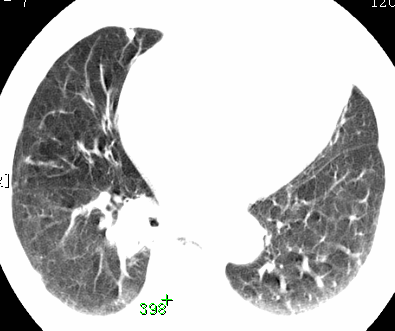

标题: CT26680:肺部右下肺静脉干结节的界定 [打印本页]

标题: CT26680:肺部右下肺静脉干结节的界定

经追查说有支扩咯血病史,但不确定

考虑1、周围型肺癌,2肺静脉畸形,前者可能大,建议增强检查。

考虑1、周围型肺癌,2肺静脉畸形,前者可能大,建议增强检查。支持!

不排除右肺下叶周围型肺癌可能。